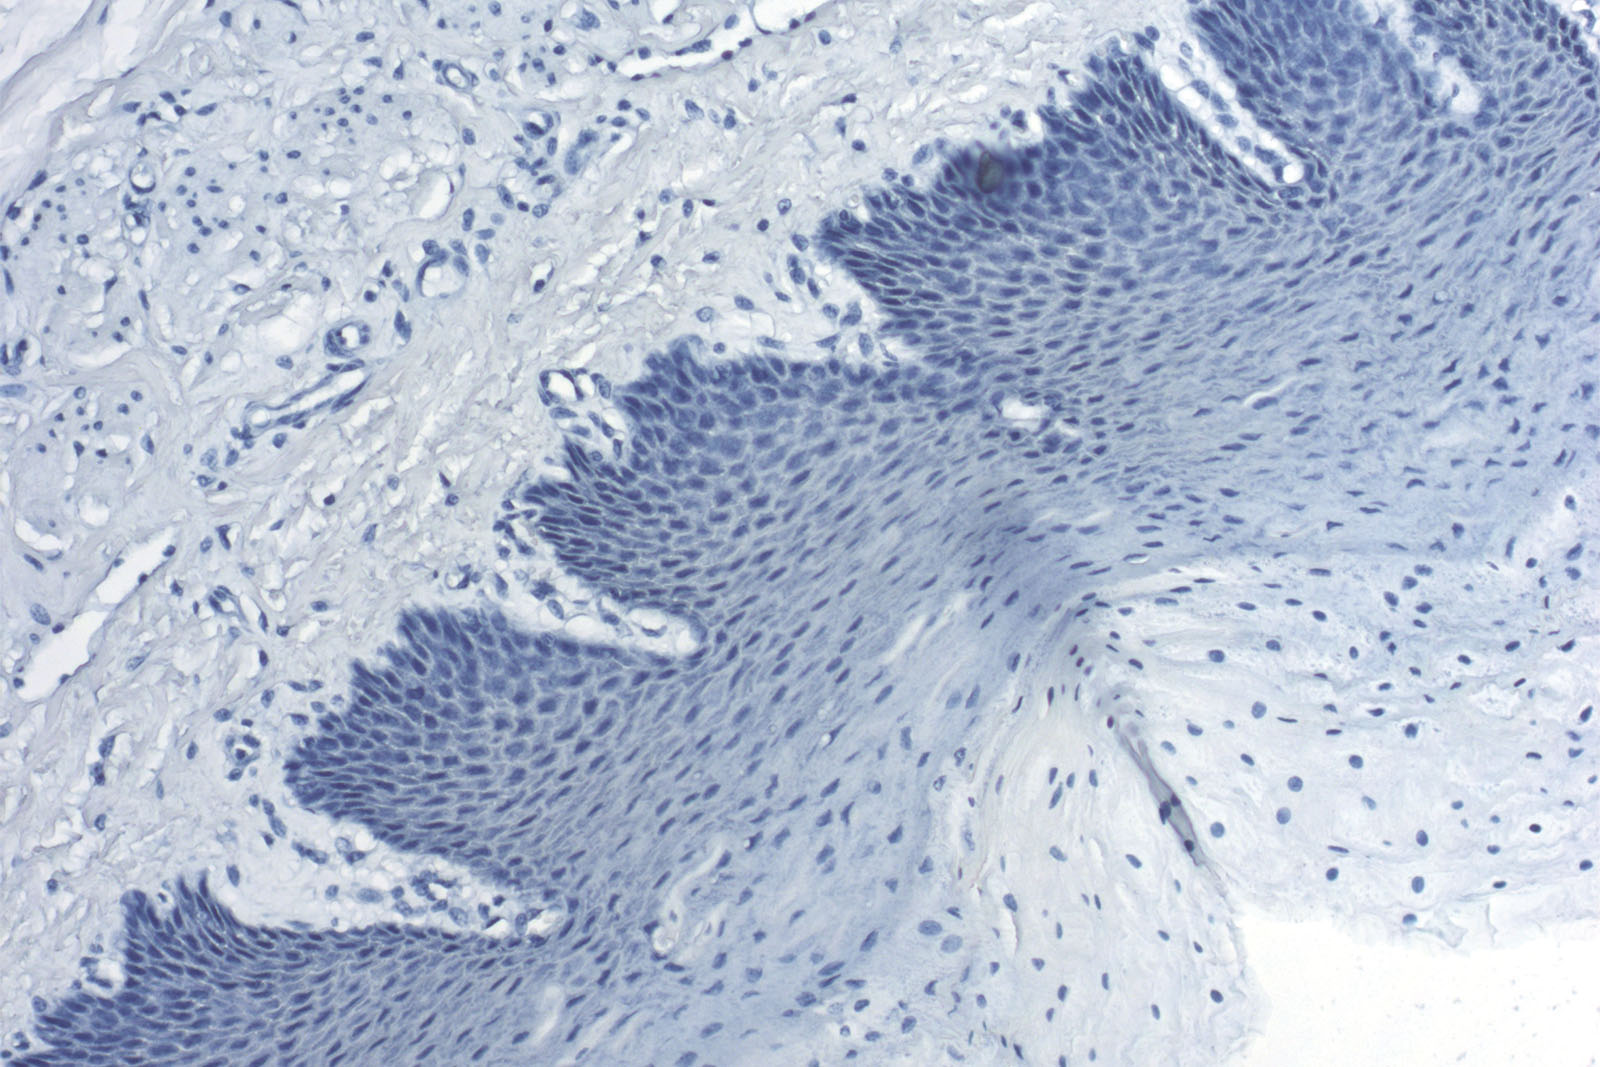

Acid-resistant hematoxylin according to Weigert

Two-reagent kit, stains nuclei blue-black

Nuclei - blue-purple (if the slide is stained only with Hematoxylin acc. to Weigert).

Combined with special staining kits, nuclei turn blue-black